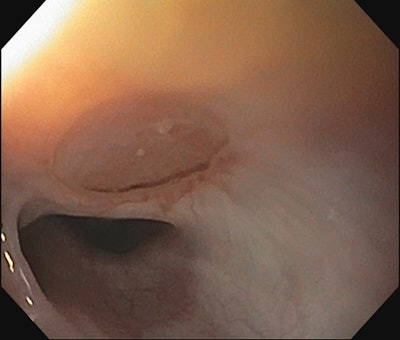

Acquired fistulas can occur related to iatrogenic injury from tracheostomy tube placement or intubation injury. They can also occur as a result of caustic ingestion or button battery ingestion. When the defect is large, but the esophagus is otherwise patent above and below the fistula, a modified slide tracheal resection technique can be used to effectively repair both the esophagus and trachea. In this technique, the trachea is transected in a beveled fashion above and below the proximal and distal aspect of the defect respectively. The tracheal wall overlying the defect is then trimmed and left pedicled to the lateral aspect of the fistula and flipped down in a trap door fashion to close the esophageal defect (Figure 2). An interposition graft is then placed, and the tracheal anastomosis is performed.

Figure 2. EGD following repair of TEF using pedicled tracheal wall and slide tracheoplasty.